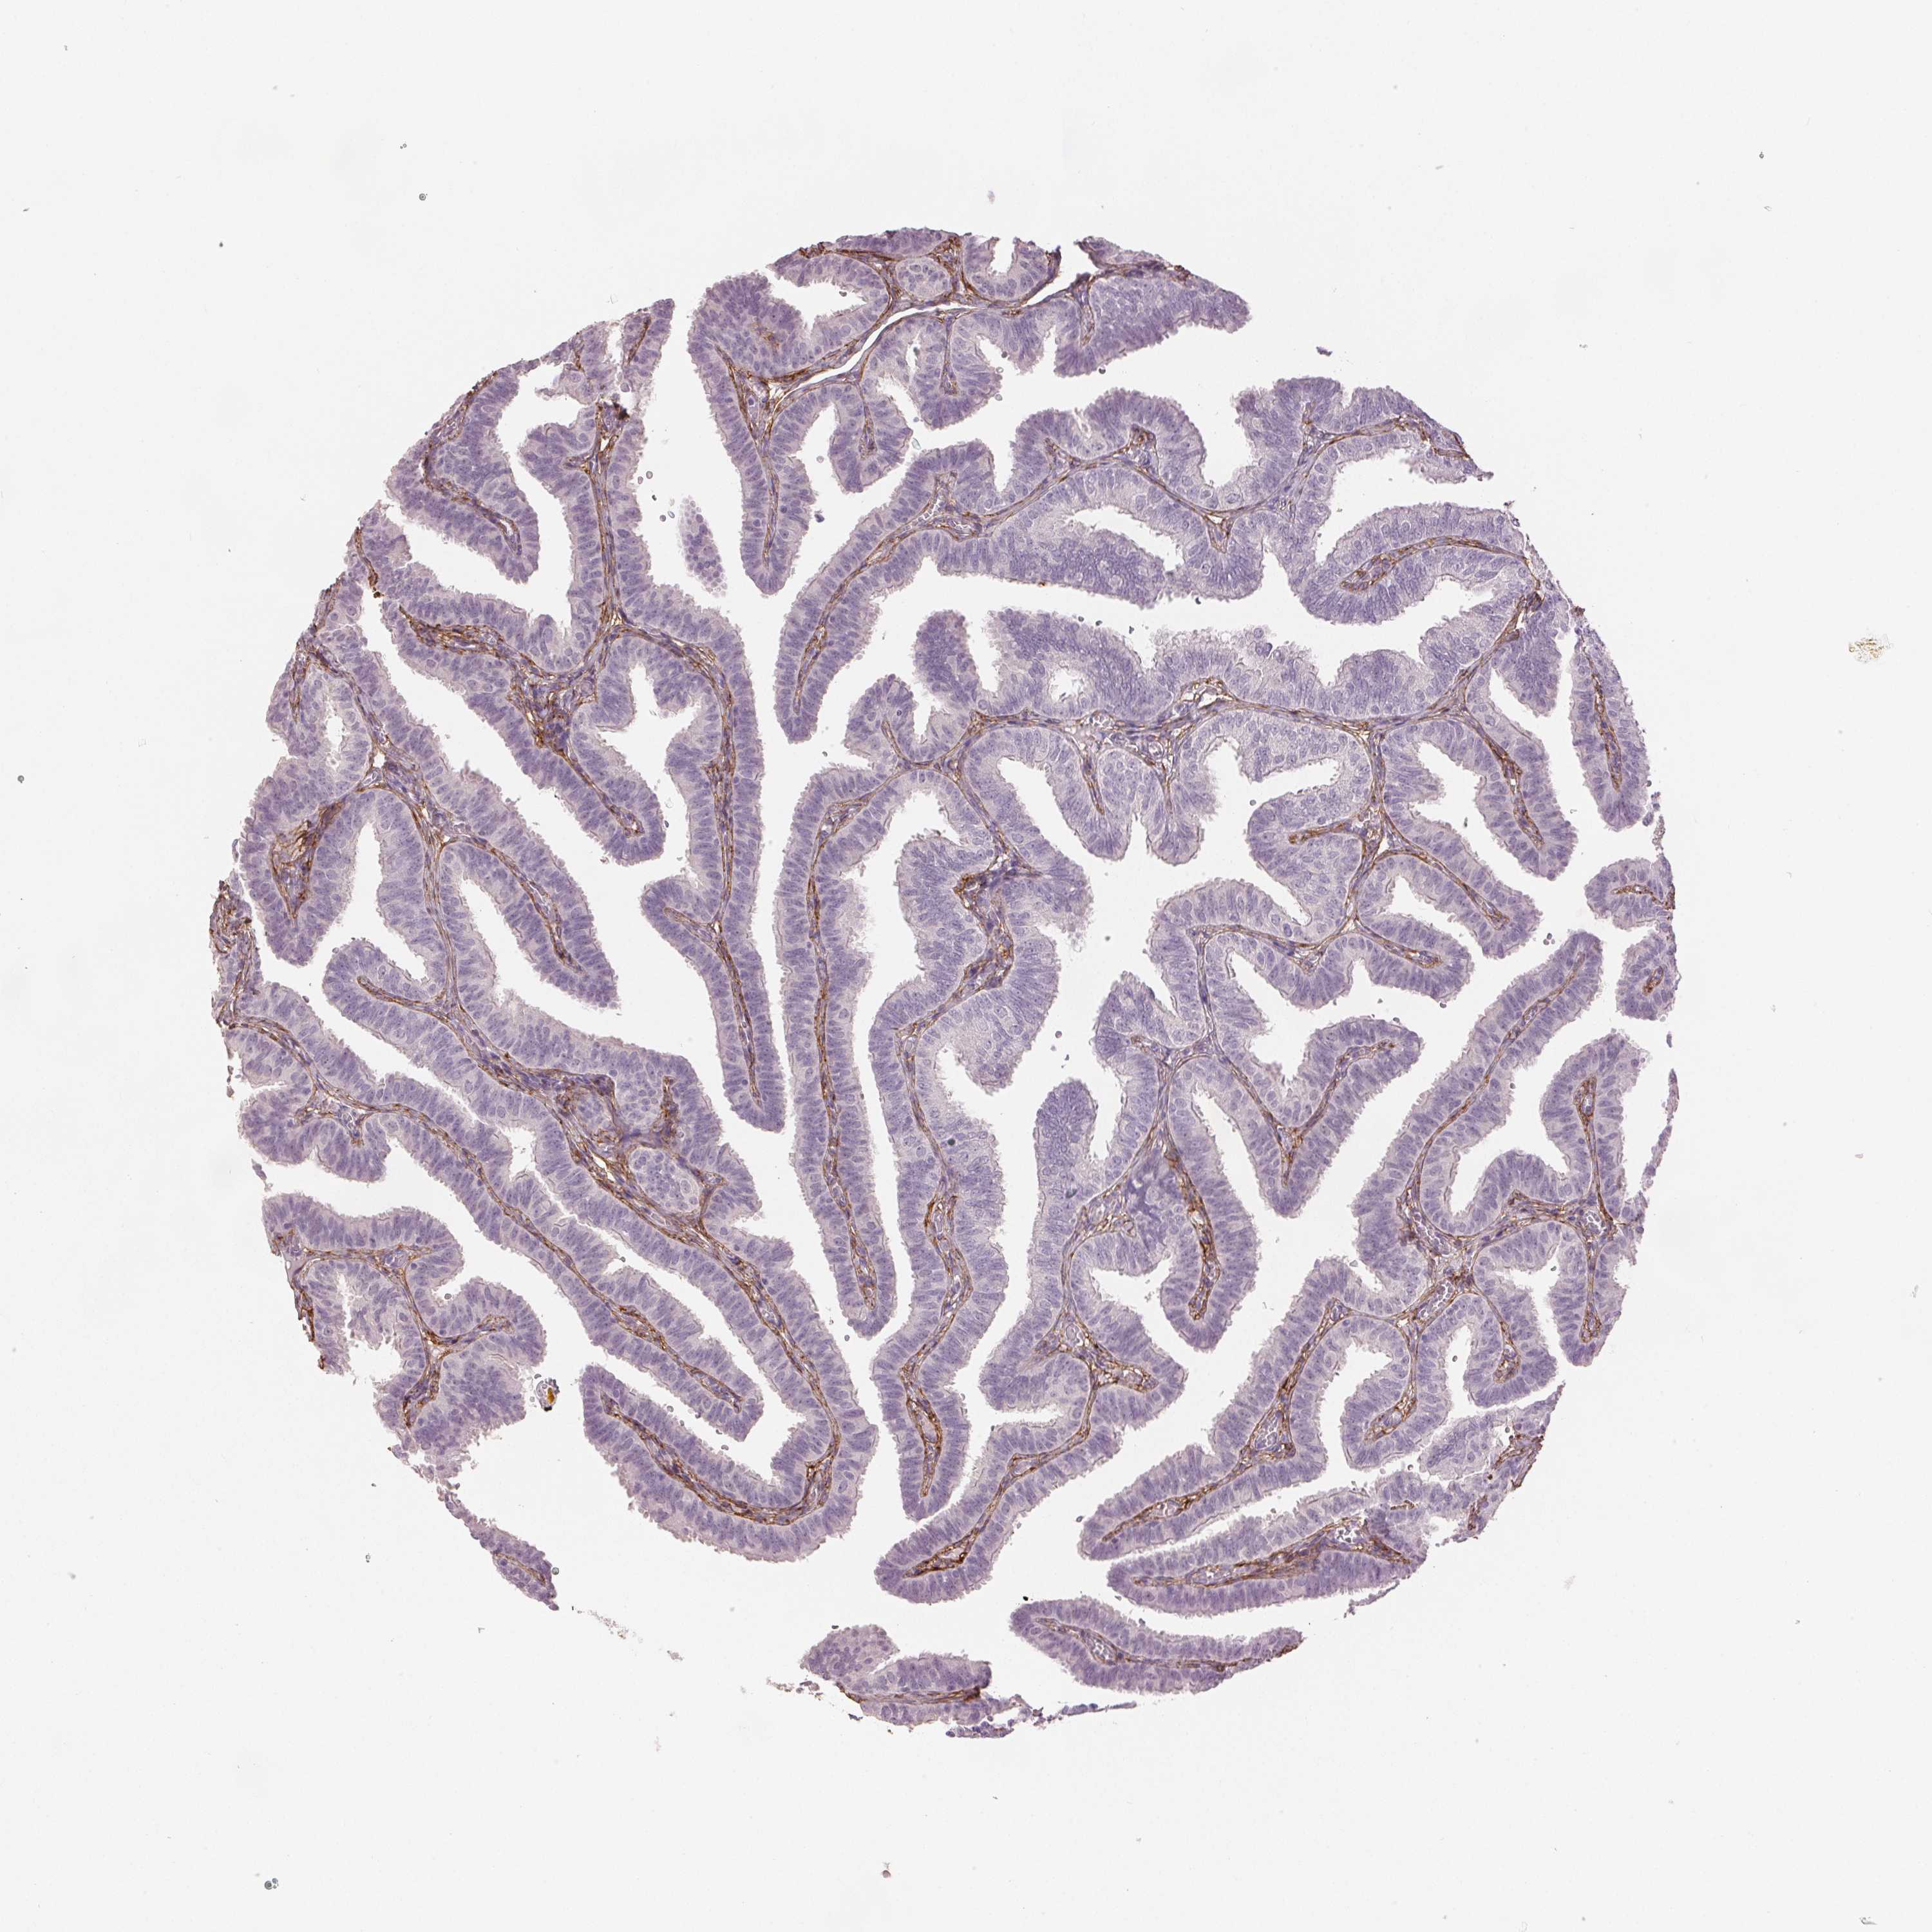

FALLOPIAN TUBE - Antibody stainingi

Antibody staining in the annotated cell types in the current human tissue is reported as not detected, low, medium, or high, based on conventional immunohistochemistry profiling in selected tissues. This score is based on the combination of the staining intensity and fraction of stained cells.

Each image is clickable and will lead to virtual microscopy that enables deeper exploration of all samples and also displays staining intensity scores, fraction scores and subcellular localization as well as patient and tissue information for each sample.

Antibody HPA017759Antibody HPA021057Antibody CAB002670Antibody CAB058696Antibody CAB068188Antibody CAB080202

Glandular cells LowNot detectedNot detectedNot detectedNot detectedNot detected